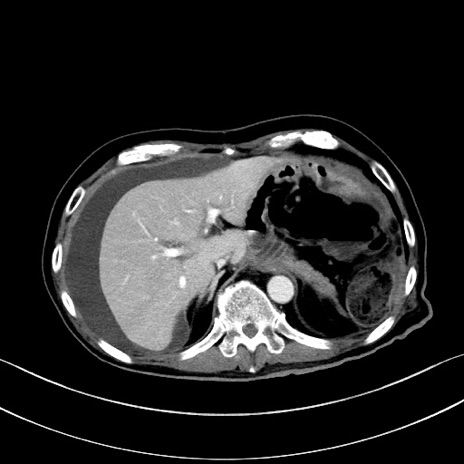

冠状断像

【症例】60歳代男性

【主訴】嘔吐

【現病歴】胃癌にて胃全摘後。食思不振が悪化し、夜中に嘔吐することがある。

【既往歴】胃癌、胃全摘、脾摘、胆摘後

【データ】WBC 5900、CRP 10.56